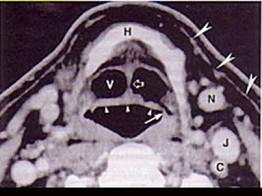

男,55岁,声嘶6年,有长期吸烟史。检查:无呼吸困难。喉镜检查:声带慢性充血,可见右侧声带可见菜花样新生物,右侧声带活动固定,喉部CT检查如下图:诊断...

问题 男,55岁,声嘶6年,有长期吸烟史。检查:无呼吸困难。喉镜检查:声带慢性充血,可见右侧声带可见菜花样新生物,右侧声带活动固定,喉部CT检查如下图: 诊断首先考虑 ( )